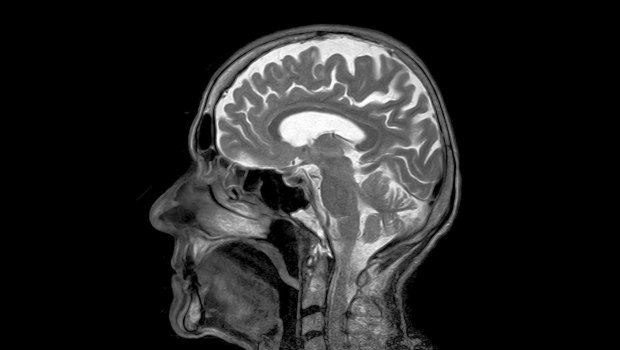

5-ALA: Η νέα εποχή στη χειρουργική των όγκων του εγκεφάλου

Νικόλαος Καραγεώργος Διευθυντής Νευροχειρουργικής, Ιατρικό Κέντρο Αθηνών Οι όγκοι του εγκεφάλου αποτελούν μία από τις πιο δύσκολες προκλήσεις της σύγχρονης ιατρικής.

Δεν απειλούν μόνο τη ζωή, αλλά και τις βασικές λειτουργίες του ανθρώπου — τη σκέψη, την ομιλία, την κίνηση, τη μνήμη.

Η αφαίρεσή τους απαιτεί ακρίβεια χιλιοστού, αφού κάθε επιπλέον χειρισμός θα μπορούσε να επηρεάσει κρίσιμες περιοχές του εγκεφάλου.

Γι’ αυτό και η εξέλιξη των τελευταίων χρόνων στη νευροχειρουργική, με τη χρήση της ουσίας 5-ALA (5-αμινολεβουλινικό οξύ), θεωρείται επανάσταση.

Η τεχνική αυτή, γνωστή και ως φθορίζουσα χειρουργική, δίνει στον χειρουργό τη δυνατότητα να “βλέπει” τον όγκο με εντυπωσιακή ευκρίνεια, μειώνοντας τον κίνδυνο να παραμείνουν καρκινικά κύτταρα ή να τραυματιστεί υγιής εγκεφαλικός ιστός.googletag.cmd.push(function() { googletag.display("300x250_m1"); }); Τι ακριβώς είναι το 5-ALA; Το 5-ALA είναι μια φυσική ουσία που μετατρέπεται μέσα στα καρκινικά κύτταρα σε προτοπορφυρίνη IX — μια χρωστική που φθορίζει όταν εκτεθεί σε ειδικό μπλε φως.